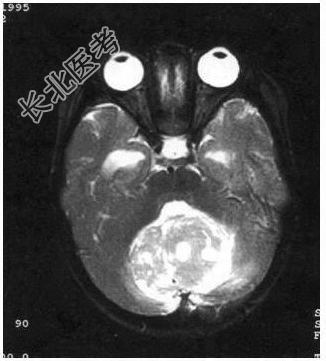

病历摘要:患儿男性,11岁。半年前开始出现行走不稳,常无故跌倒。半月前出现发作性剧烈头痛,伴恶心呕吐。体检:T36℃,P100次/分,R22次/分,BP100/60mmHg,神清,言语较缓慢,双眼外展约不及边,双眼侧视时有小幅度水平眼震。四肢肌力正常,右上肢肌张力较低,坐位姿势不稳,常不自主摇晃,双上肢指鼻不准,行走蹒跚步态,足距扩大,身前倾。患儿行头颅MR检查(见图)